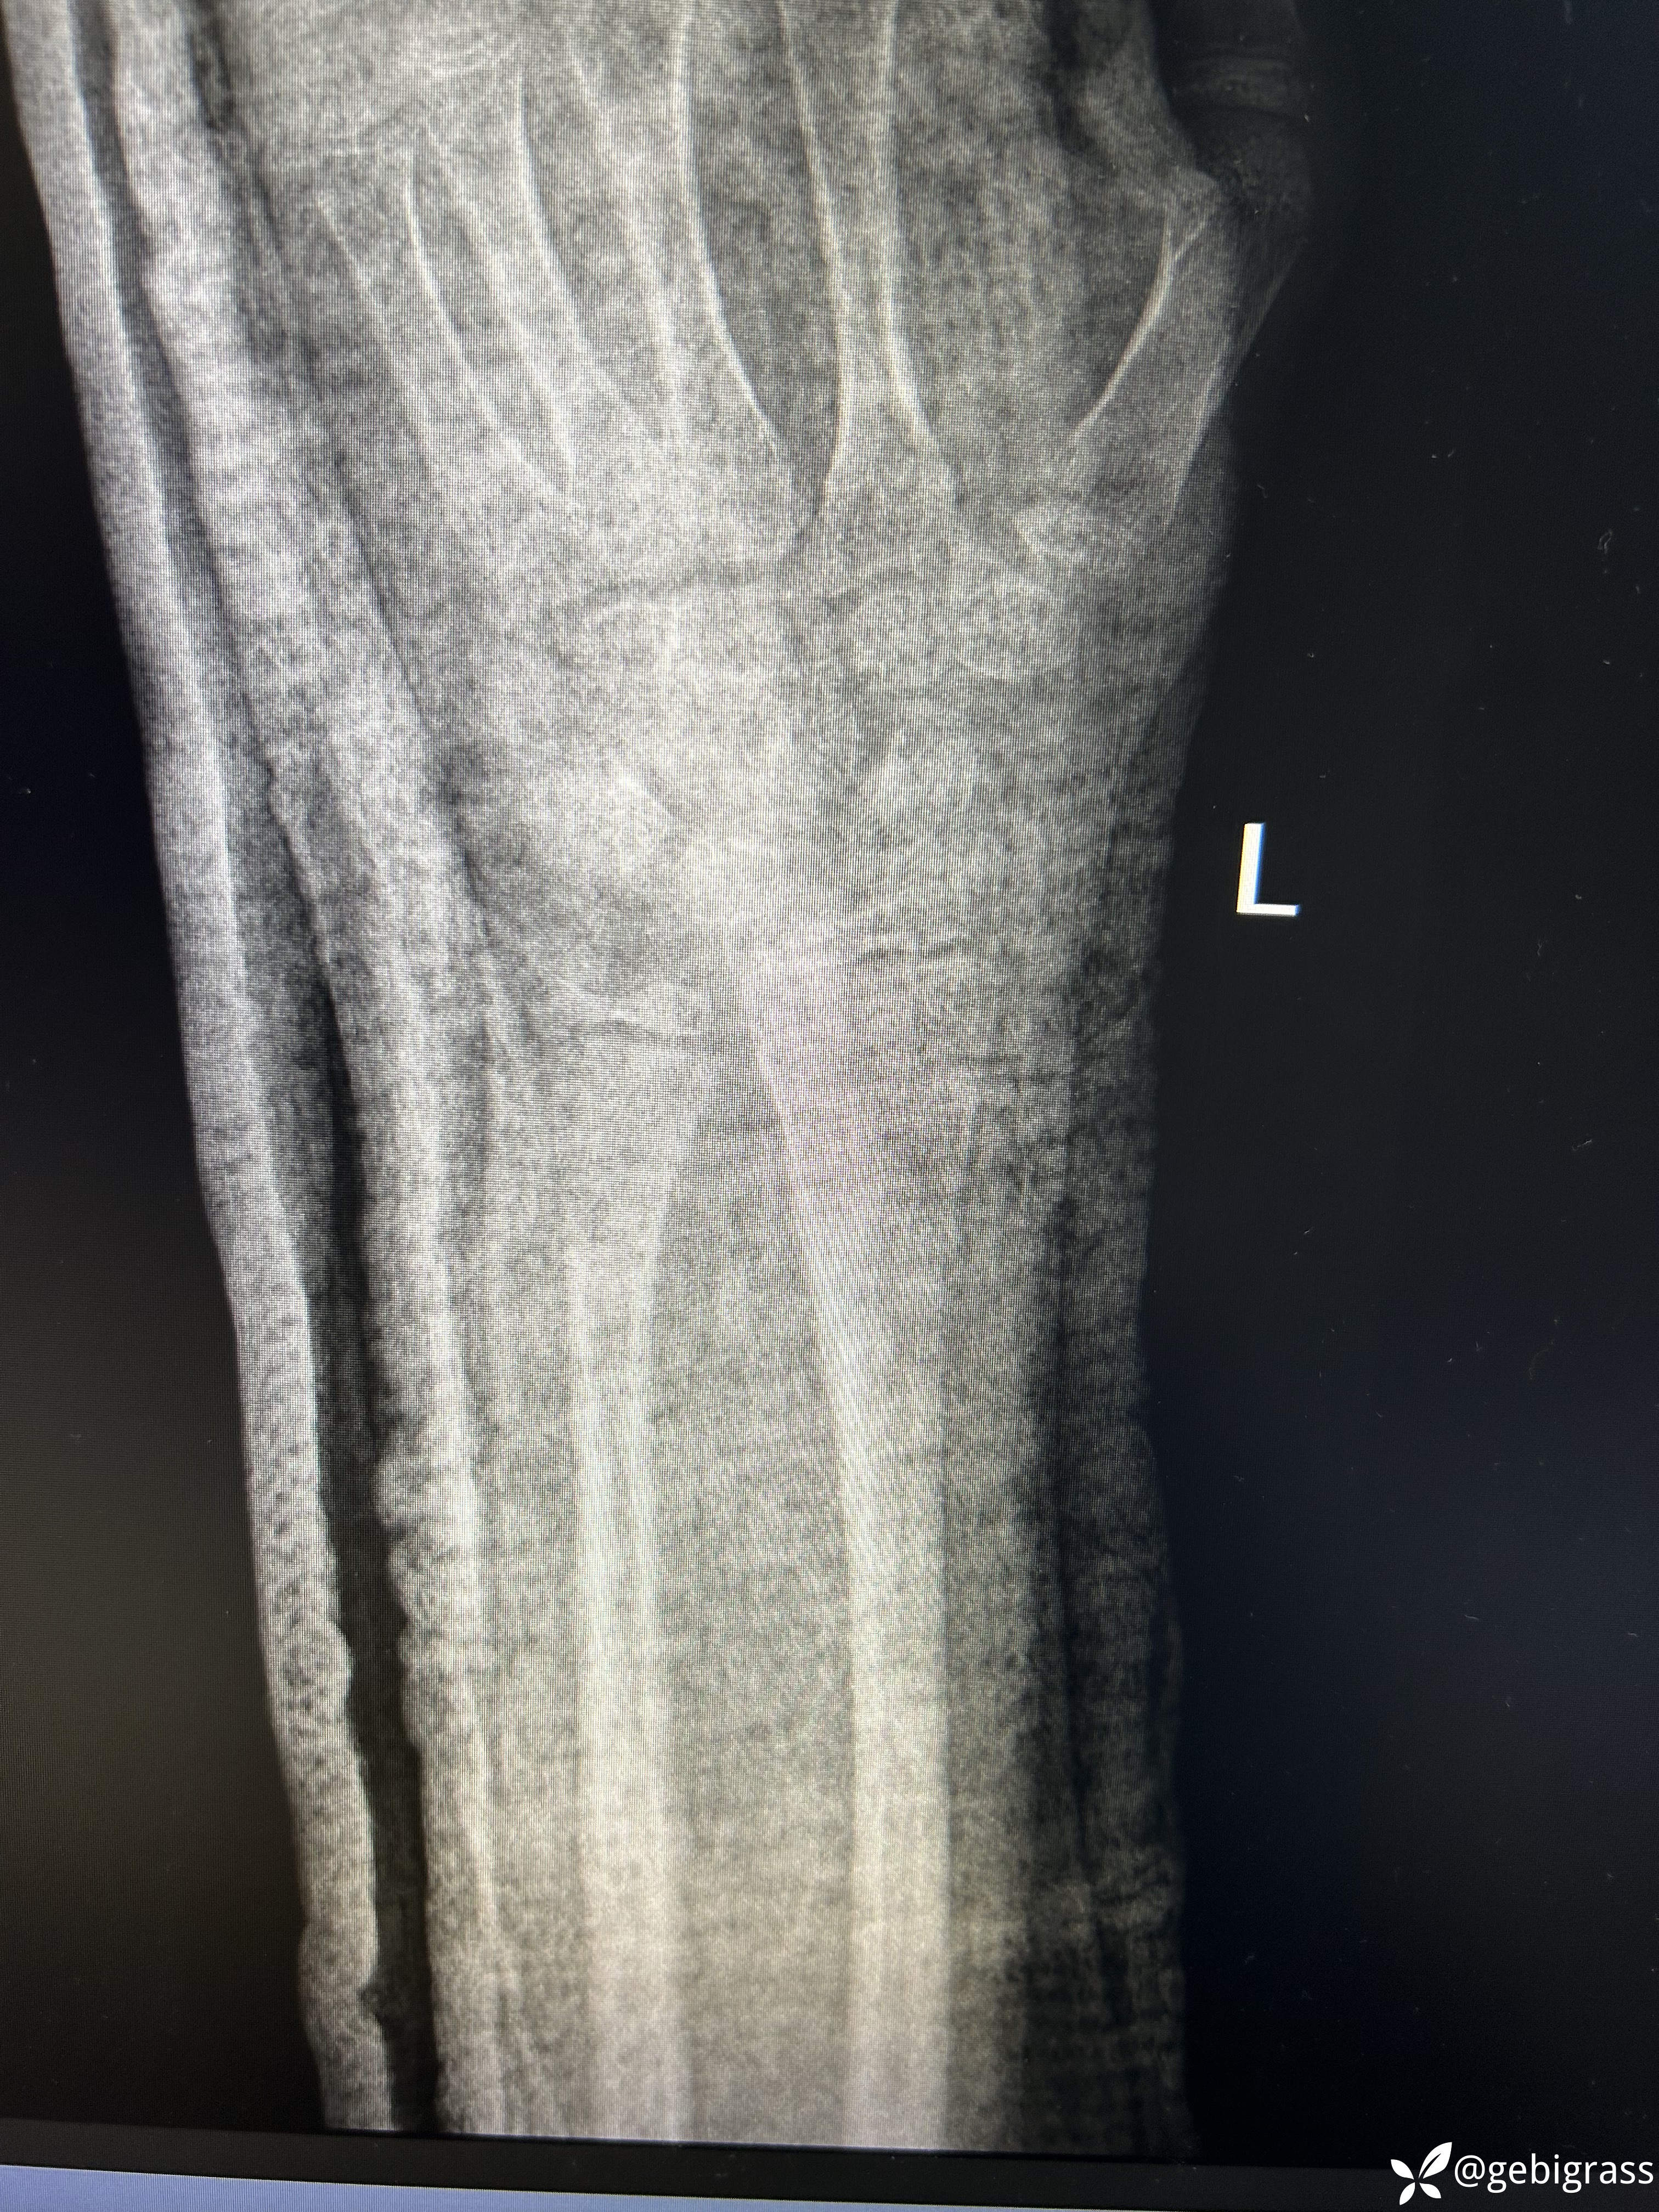

复位后1周:

复位后两周:

1.儿童不是成人的缩小版,塑型能力强大。

2.对于儿童桡骨远端骨折,夹板更合适。